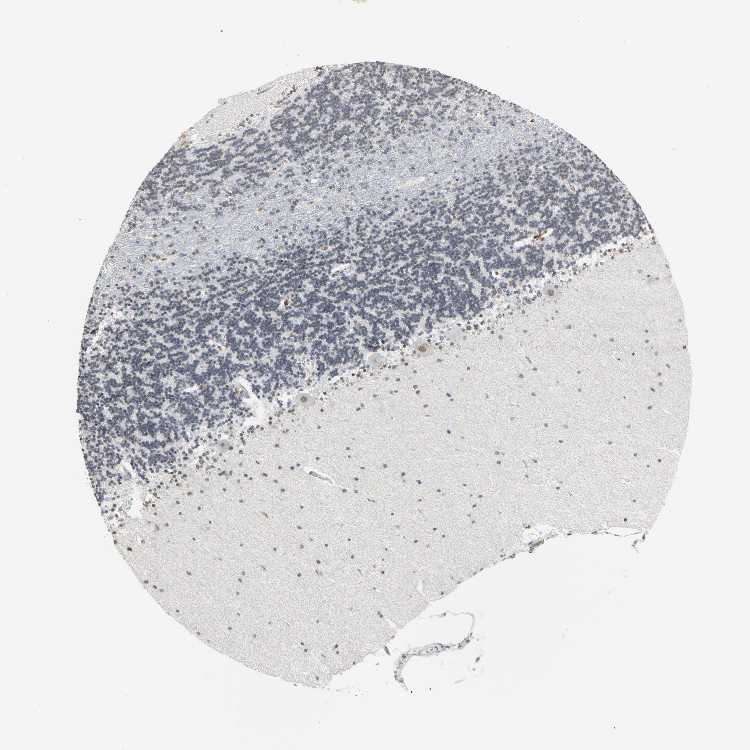

BRAIN CEREBELLUM Show tissue menu

CEREBELLUM - Antibody stainingi

Antibody staining in the annotated cell types in the current human tissue is reported as not detected, low, medium, or high, based on conventional immunohistochemistry profiling in selected tissues. This score is based on the combination of the staining intensity and fraction of stained cells.

Each image is clickable and will lead to virtual microscopy that enables deeper exploration of all samples and also displays staining intensity scores, fraction scores and subcellular localization as well as patient and tissue information for each sample.

Antibody HPA004098

Bergmann glia - cytoplasm/membrane Not detected

Bergmann glia - nucleus High

GLUC cells - cytoplasm/membrane Not detected

GLUC cells - nucleus Not detected

Purkinje cells - cytoplasm/membrane Not detected

Purkinje cells - dendrites Not detected

Purkinje cells - nucleus High

Granular cells - cytoplasm/membrane Not detected

Granular cells - nucleus Low

Molecular layer - neuropil Not detected

Molecular layer cells - cytoplasm/membrane Not detected

Molecular layer cells - nucleus Medium

Processes in granular layer Not detected

Processes in molecular layer Not detected

Processes in white matter Not detected

Synaptic glomeruli - capsule Not detected

Synaptic glomeruli - core Not detected

White matter cells - cytoplasm/membrane Not detected

White matter cells - nucleus Not detected